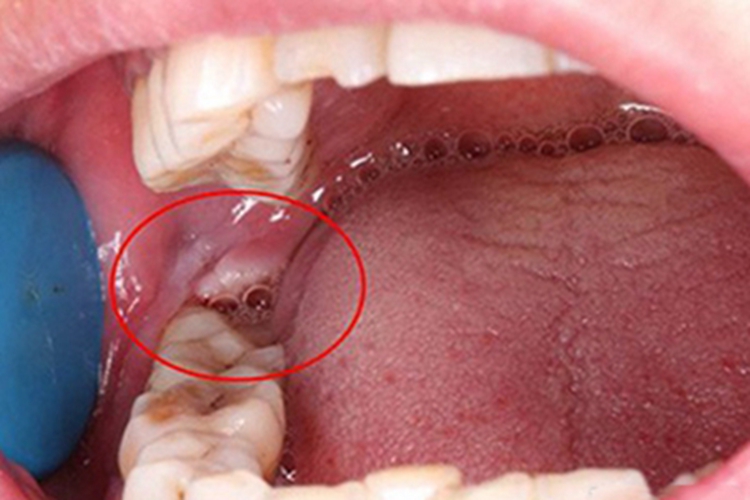

3、肉芽组织形成阶段:在炎症逐渐消退的同时,创口内开始形成肉芽组织,肉芽组织由新生的毛细血管、成纤维细胞和炎性细胞组成,它能够填充创口,为后续的组织修复奠定基矗

4、骨组织重建阶段:随着肉芽组织的成熟,骨组织开始重建,新的骨细胞逐渐取代肉芽组织,使牙槽骨的结构和强度逐渐恢复,这个过程相对较慢,需要较长时间。